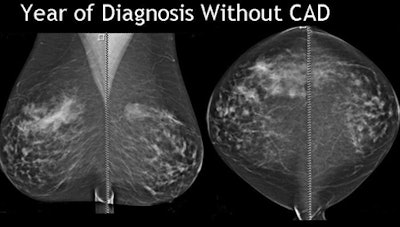

The study evaluated the effectiveness of digital mammography CAD in marking breast cancers both at diagnosis and in prior years' scans. The retrospective review examined all interval missed cancers from 2004-2008, Destounis said.

Retrospective review of interval and missed cancers imaged with full-field digital mammography (FFDM) between 2004 and 2008 revealed 60 cancer cases that fulfilled the study criteria. The cohort was a mixture of screening and diagnostic cases, all of which had CAD evaluation at the time of diagnosis available for review.

At diagnosis CAD marked 78% (47) of the cancers, Destounis said. CAD marked 70% of the masses, 80% of masses with calcium, and missed the case of architectural distortion.

Overall, CAD marked the cancer 78% of the time, and cancer in prior year(s) 40% of the time, she said. So the study showed that even when CAD marked the lesion of interest, radiologists continue to disregard the CAD marks frequently, she said. Why is this happening?